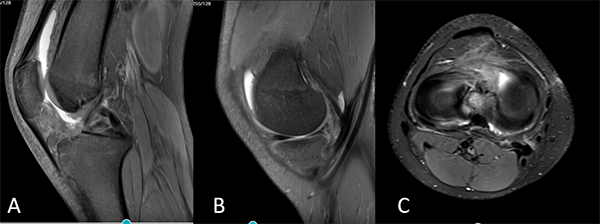

El seguimiento postoperatorio comenzó con inmovilización de la rodilla por cuatro semanas con una férula inguinomaleolar, se permitieron ejercicios isométricos y de movilidad pasiva asistida 0-40° hasta la sexta semana, luego 0-90° hasta la octava semana. Al tercer mes se solicitó RM de control en la que se verificó reducción anatómica y consolidación de la fractura de espina tibial; menisco interno normoposicionado y de buena señal (figs. 7 y 8).

Figura 7: Resonancia de control. Cortes coronales, reducción anatómica y consolidación de la fractura de espina tibial. Menisco interno normoposicionado y de buena señal.

Figura 8: A) Corte sagital, LCA de buena señal, reducción de la fractura, material de fijación en espina tibial. B-C) Cortes sagital y axial. Menisco interno normoposicionado, cambios de señal vinculados a sutura meniscal.